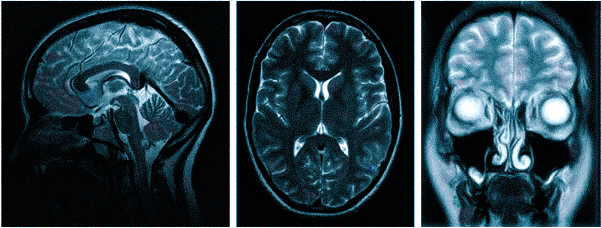

Боль при шейном остеохондрозе изначально возникает в затылке, а по мере прогрессирования патологии распространяется на лобно-височную область головы

Болевой синдром при различных патологиях имеет разную интенсивность, локализацию, длительность и может сопровождаться рядом других неприятных симптомов: тошнотой, выпадением полей зрения, потерей сознания и пр. Цефалгия развивается самостоятельно или сопутствует какому-либо состоянию. Специалисты едины во мнении: если регулярно беспокоит ноющая, мигренеподобная, распирающая и другая головная боль в темечке, затылке, висках, следует обратиться на очную консультацию и пройти первичную диагностику: